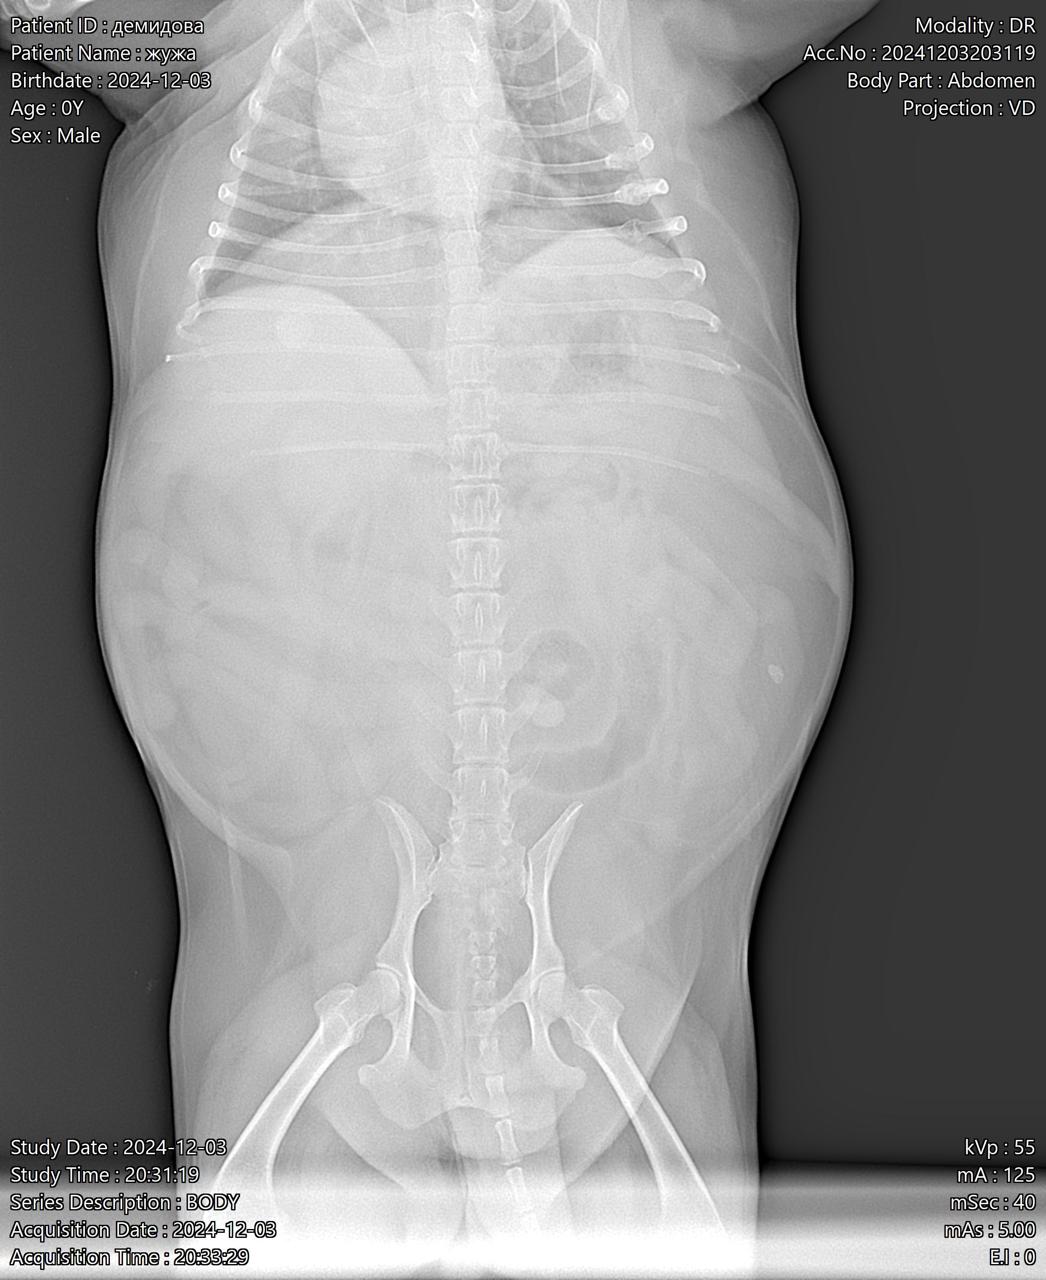

Москва, цверг Жужа, 7 лет

Визит к врачу с поносом